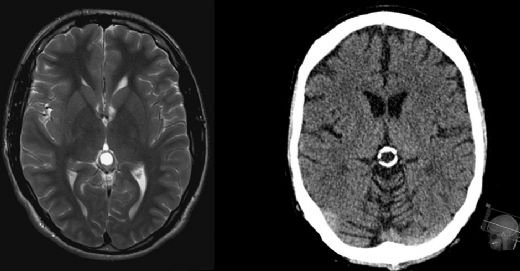

Doğuştan Beyinde Kist Belirtileri ve TedavisiDoğuştan beyinde kist, genellikle doğum öncesi veya doğum sırasında gelişen ve beyinde sıvı dolu boşlukların oluşumu ile karakterize edilen bir durumdur. Bu kistlerin büyüklüğü, sayısı ve konumu, bireyde farklı semptomlar ve komplikasyonlar yaratabilir. Bu makalede, doğuştan beyinde kistlerin belirtileri, tanı yöntemleri ve tedavi seçenekleri detaylı bir şekilde ele alınacaktır. Doğuştan Beyinde Kist Nedir? Doğuştan beyinde kist, beynin normal yapısında meydana gelen anormallikler sonucu oluşan sıvı dolu keseciklerdir. Bu kistler, genellikle gelişimsel anomali, enfeksiyonlar veya genetik faktörler nedeniyle ortaya çıkabilir. Kistlerin varlığı, beyindeki normal işlevleri etkileyebilir ve çeşitli nörolojik semptomlara yol açabilir. Belirtiler Doğuştan beyinde kistlerin belirtileri, kistin büyüklüğüne, yerine ve bireyin yaşına bağlı olarak değişiklik gösterebilir. Genel olarak gözlemlenen belirtiler şunlardır:

Bu belirtiler, kistin büyümesi veya beyindeki basıncı artırması durumunda daha belirgin hale gelebilir. Tanı Yöntemleri Doğuştan beyinde kistlerin tanısı, genellikle görüntüleme teknikleri kullanılarak konulmaktadır. Bu yöntemler arasında:

Bu görüntüleme yöntemleri, kistin boyutunu, yerini ve etkilerini değerlendirmek için kullanılır. Ayrıca, kistin nedenini belirlemek için kan testleri ve genetik incelemeler de yapılabilir. Tedavi Seçenekleri Doğuştan beyinde kistlerin tedavisi, kistin büyüklüğüne, semptomların ciddiyetine ve bireyin genel sağlık durumuna bağlı olarak değişir. Tedavi seçenekleri şunları içerebilir: